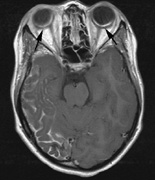

1. Schwannomas most commonly affect the fifth cranial nerve (CN), but any cranial nerve may be affected. In contrast to vestibular schwannomas (CN VIII), these typically do not grow large.84,90 Vestibular schwannomas (acoustic neuromas) are the classic finding in NF2 (Fig. 7). The risk for malignant transformation is low, but may be higher with radiation exposure.84,94

3. Other tumors: low-grade ependymomas and gliomas may affect the cervical spine and Brainstem (Fig. 7).84

Fig. 7. Neurofibromatosis type 2: Images of a 12-year-old boy with deafness and weakness in his arms and legs, whose father has bilateral deafness. Axial T2-weighted (a) and postcontrast axial (b) T2-weighted images reveal bilateral vestibular schwannomas, which are also known as acoustic neuromas (arrows). This is the classic finding of NF2. (b, c) Bilateral schwannomas are seen in Meckel's cave (arrowheads) and a (d) lower left cranial nerve schwannoma extends into the pars nervosa of the jugular foramen (arrow). (e) A part cystic and part solid enhancing ependymoma in seen within the cervical cord and medulla and within the distal cord and conus. (e, f) Thoracic schwannomas are present at numerous levels (arrowheads). Marked enhancement and thickening of the roots within the cauda equina also represent multiple schwannomas.